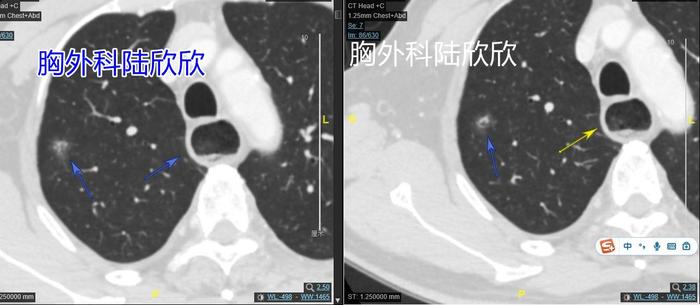

上图,可见右上肺一个12毫米的混合磨玻璃结节,结节的实性成分像海里的珊瑚礁。上面两张图同时可见肺结节平面的食管近端扩张。